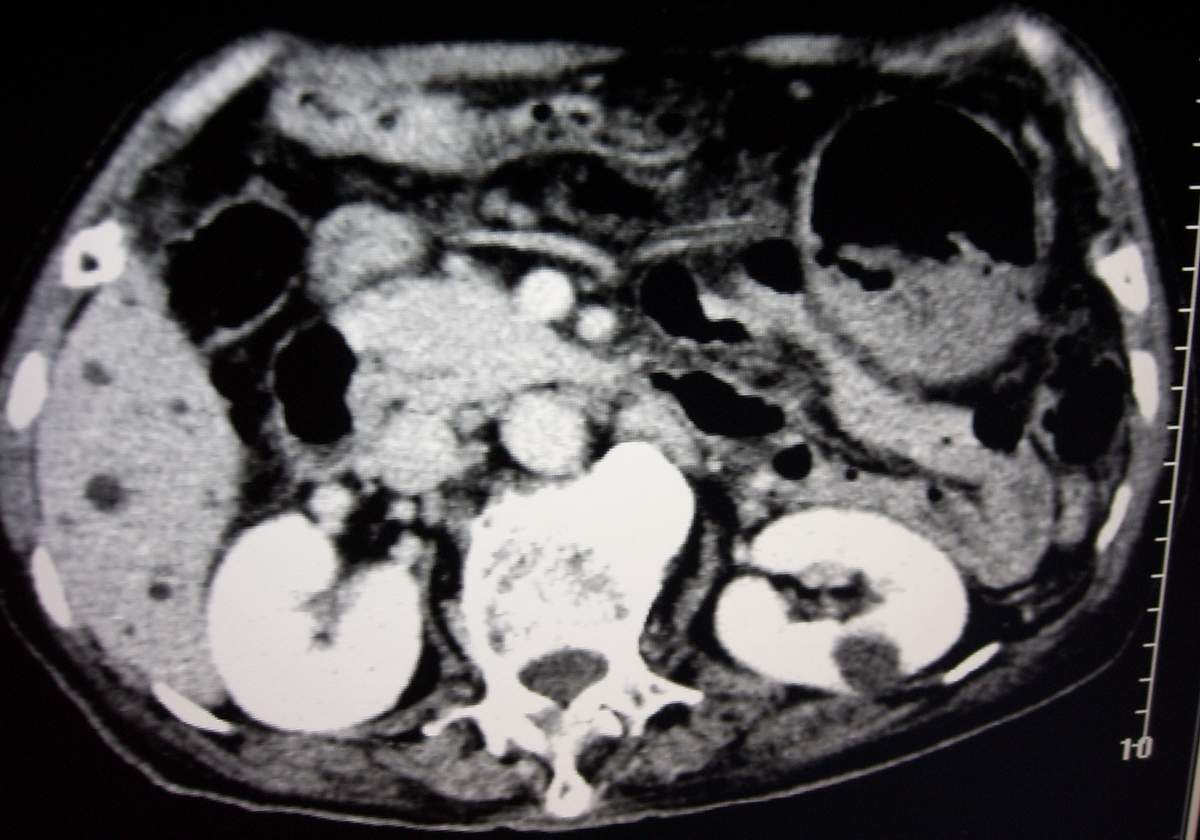

男,77岁,病史不详。

肝内胆管扩张、主胰管扩张 ,胰头影大,考虑胰头癌或胆管下端癌侵犯胰腺可能性大

另外见:胆囊结石 左肾囊肿

肝内外胆管明显扩张,但是程度较轻,应该是个慢性的过程,增强扫描后未见明显异常强化,胰管增宽、扩张考虑为胰头部占位性病变。

慢性胆囊炎,胆结石,左肾囊肿,胰头癌伴肝内胆管、胰管扩张,不除外侵犯肠系膜上静脉的可能。

肝内外胆管明显扩张,肝门区见软组织密度肿块,胆囊壁增厚,胆囊扩大。胰头不大。考虑:肝门区胆管细胞癌。

肝内胆管扩张明显,cbd未见明显扩张,胰管轻度扩张,肝门部胆总管癌?

肝内胆管普遍扩张,呈串珠状改变,走行不规则,且右叶胆管周围肝实质密度呈条片状减低,未见占位性病变,外周胆管及胰管扩张不及肝内胆管.胰腺钩突形态正常,胰十二指肠区域未见明显结节及肿块,初步考虑慢性胆管炎可能性大.请结合临床病史.另外用宽窗看一下吉氏筋膜有无增厚.

1肝门区域软组织影,肝内胆管明显扩张,胰管轻度扩张。考虑肝门区胆管细胞癌。2胆囊结石。3左肾小囊肿。

1 肝内外胆管扩张,肝内明显,胰管扩张,胰头明显增大,符合胰头癌双管征。2 胆囊壁略增厚,胆囊内可见高密度结石影,胆囊炎、胆结石3 左肾囊肿